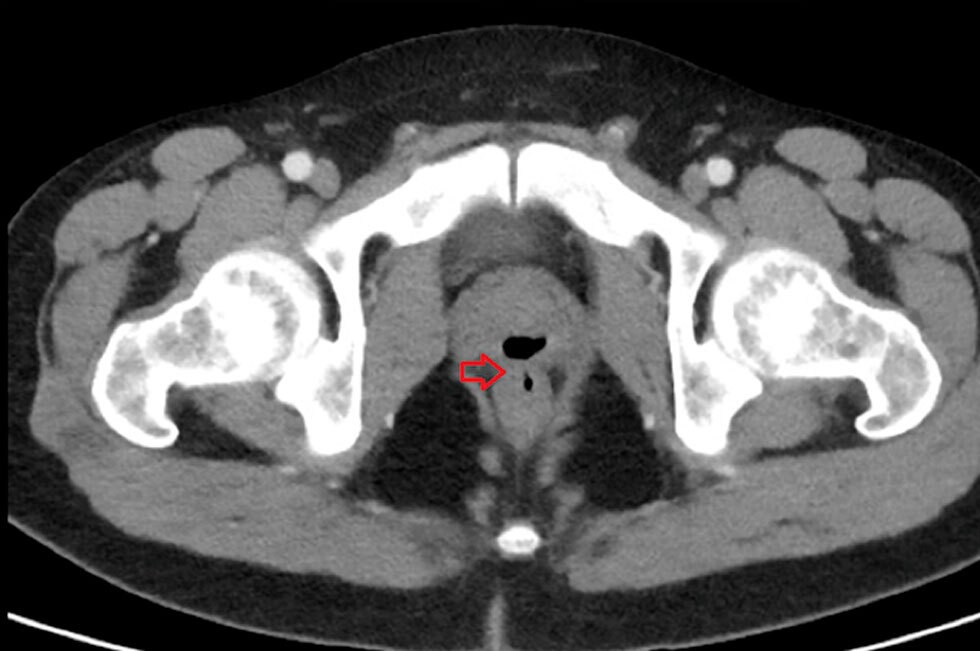

Tras los análisis, los especialistas detectaron una infección en el tracto urinario, inconvenientes en la pared rectal y una “fístula rectal-prostática”. Es decir, una lesión anormal entre la uretra y el recto, a través de la cual estaban pasando algunos líquidos y sólidos. Fue tratado con medicamentos y le realizaron una intervención quirúrgica.